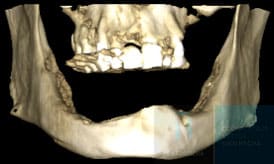

Antes de la cirugía se realiza un estudio individualizado de cada paciente mediante pruebas de imagen avanzadas como la tomografía computarizada (CBCT) y escaneados intraorales. Gracias a la mejora del diseño y la fabricación digital asistida por ordenador, podemos conocer al detalle la anatomía ósea y diseñar un plan de tratamiento personalizado para la colocación del implante yuxtaoseo.

Con la información obtenida del estudio, el equipo diseña de forma digital los implantes a medida y se planifica su posición sobre la pantalla del ordenador. A partir de este diseño, se fabrican unas férulas quirúrgicas que guiarán la colocación del implante subperióstico durante la cirugía, asegurando que la estructura se adapte perfectamente al hueso del paciente.

En este caso mostramos el antes y el después de un paciente con atrofia ósea severa y la rehabilitación conseguida gracias al tratamiento de implantes subperiósticos en Valencia:

Antes

Proceso

Después